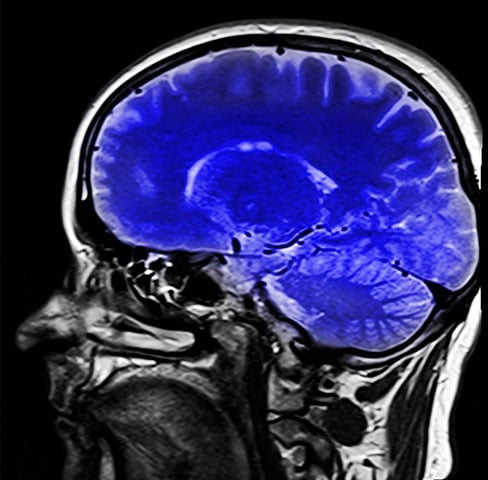

Conheça colina, nutriente vital para o bom desenvolvimento do cérebro